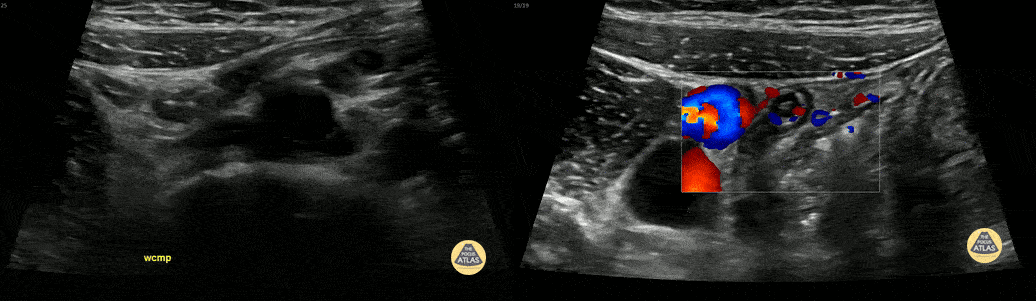

7 y/o F with abdominal pain. Normal appendix identified. Contributor: Russ Horowitz, MD, Lurie Children's Hospital